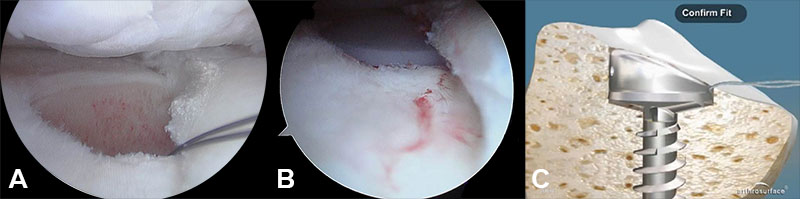

Componente tibial: el componente tibial puede ser colocado bajo asistencia artroscópica o de manera abierta bajo visualización directa.

De realizarse bajo asistencia artroscópica una vez delimitada la lesión, por el portal medial, se puede acceder fácilmente con la guía para el botón tibial, la cual se coloca en el centro de la lesión en el platillo interno. Se recomienda mantener como mínimo un margen de 5 mm de platillo tibial hacia el borde medial y 5 mm hacia el borde anterior, para asegurar un muro óseo cortical suficiente. El “template” elegido debe ser el más pequeño posible y que cubra la totalidad del defecto. Además, se debe elegir el que presente mejor contacto A/P y M/L que coincida con la curvatura del platillo (Figs. 2 y 3).

Figura 2: A: Guía de platillo tibial por visión artroscópica. B: Guía tibial montada por vía abierta.

Figura 3: A y B: Lecho del platillo que recibe al botón de polietileno por visión artroscópica. C: Esquema del acople en un corte sagital de tibia.